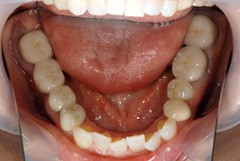

銀歯を白く

銀歯を白くしたいというお問い合わせも

多数頂くことがあります☆

見た目はもちろん、セラミックのかぶせ物は

汚れが付着しにくいので、虫歯へのリスクも少なくなります。

保険適用外にはなりますが、将来的なことや審美的なことを

考えると、セラミックのかぶせ物をおススメ致します。